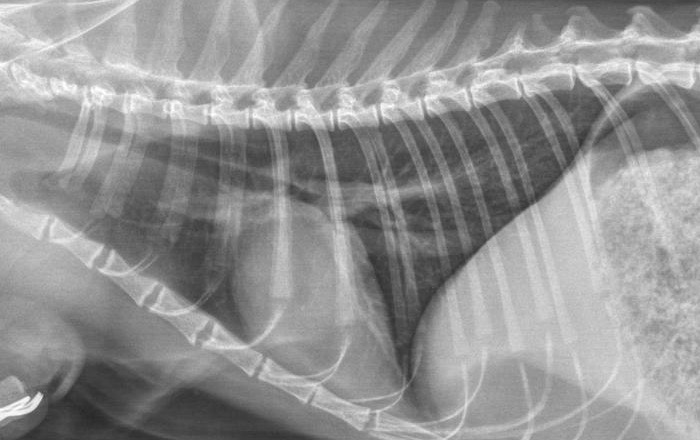

Photo de gauche : cette radio ancienne montre un

épanchement pleural, qui masque une grande partie du cœur et toute la partie crâniale du thorax (à gauche sur la radio), chez un chat de 1 an présentant une forme humide de PIF, avec également une ascite. Par comparaison, ci-dessus, une image normale du thorax chez un chat de 8 ans, également atteint de PIF, mais avec « seulement » une ascite modérée.